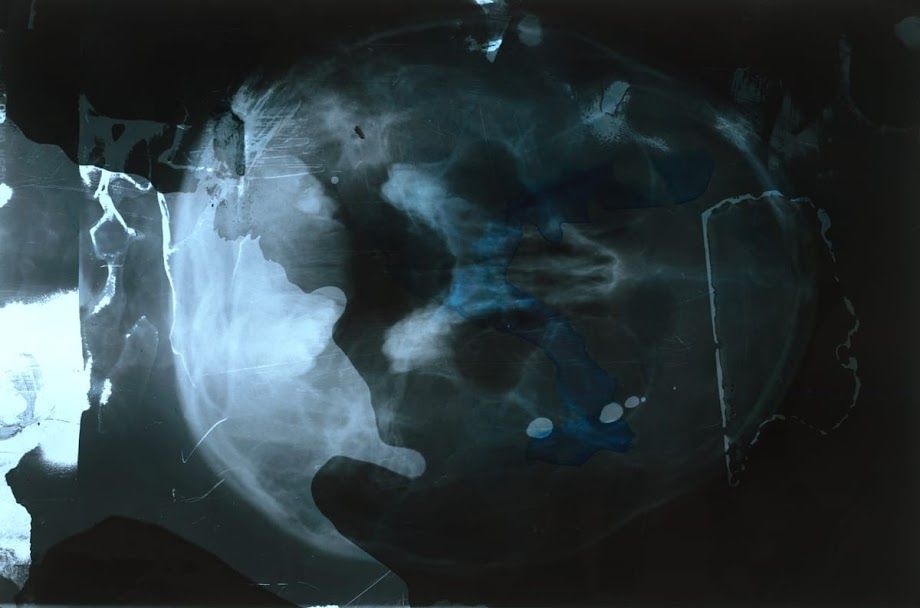

מעבר לגופות האבודות

במהלך הקורונה, לא היה לי ציוד זמין בבית לעבוד איתו.

לאחר מכן השתמשתי בצילומי רנטגן משלי, במוצרים ביתיים ובמכשירים יומיומיים.

ידעתי שהחומר המקורי, קרני הרנטגן, ייעלם, ויוחלף בתקליטורים.

אחר כך הצלחתי להשיג צילומי רנטגן נוספים ואת הדיאלוג שלי עם העקבה

והיעלמותן של הגופות הצליחה להיות משוחזרת.